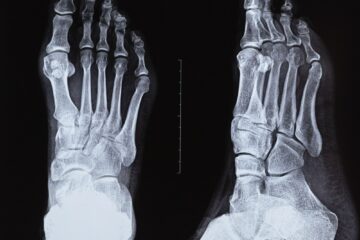

Pirmiausia gydytojas apžiūri ranką, įvertina, kada atsirado gumbas ir ar yra kitų nusiskundimų. Dažniausiai atliekama rentgeno nuotrauka, padedanti atskirti išaugą nuo kitų riešo pažeidimų. Jei reikia, galima atlikti papildomus tyrimus – ultragarsą, magnetinio rezonanso tomografiją, kartais elektromiografiją ar kompiuterinę tomografiją.